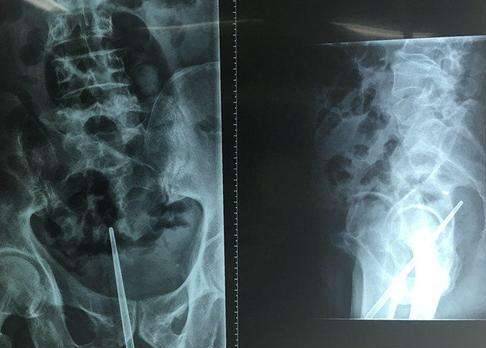

不久前,大陆杭州一名男子到医院就诊,称自己这几天肚子痛,小便困难。医生为他照X光,本来想看看他的泌尿系统是否病变,没想到竟然看到了难以置信的一幕。一根约18cm长的不鏽钢筷子直直插在牠的尿道中,看起来非常诡异。

▼他準备用筷子将尿道撑开,看看有没有断裂。没想到不锈钢筷子越塞越里面,最后竟然拔不出来。他终于意识到问题的严重性,慌忙来到医院。就诊时因为觉得难为情,他还是没有说出实情,直到拍片后,医生才发现真相。

▼医生表示,因为筷子位置靠里,只能通过手术取出。手术中,他们发现筷子从前列腺穿出,又从膀胱间隙穿出,把腹膜戳破,直到直肠壁才停下。幸好直肠没有破裂,如果筷子穿行过程中戳破大血管,甚至会引发大出血、休克,患者还有可能死亡。